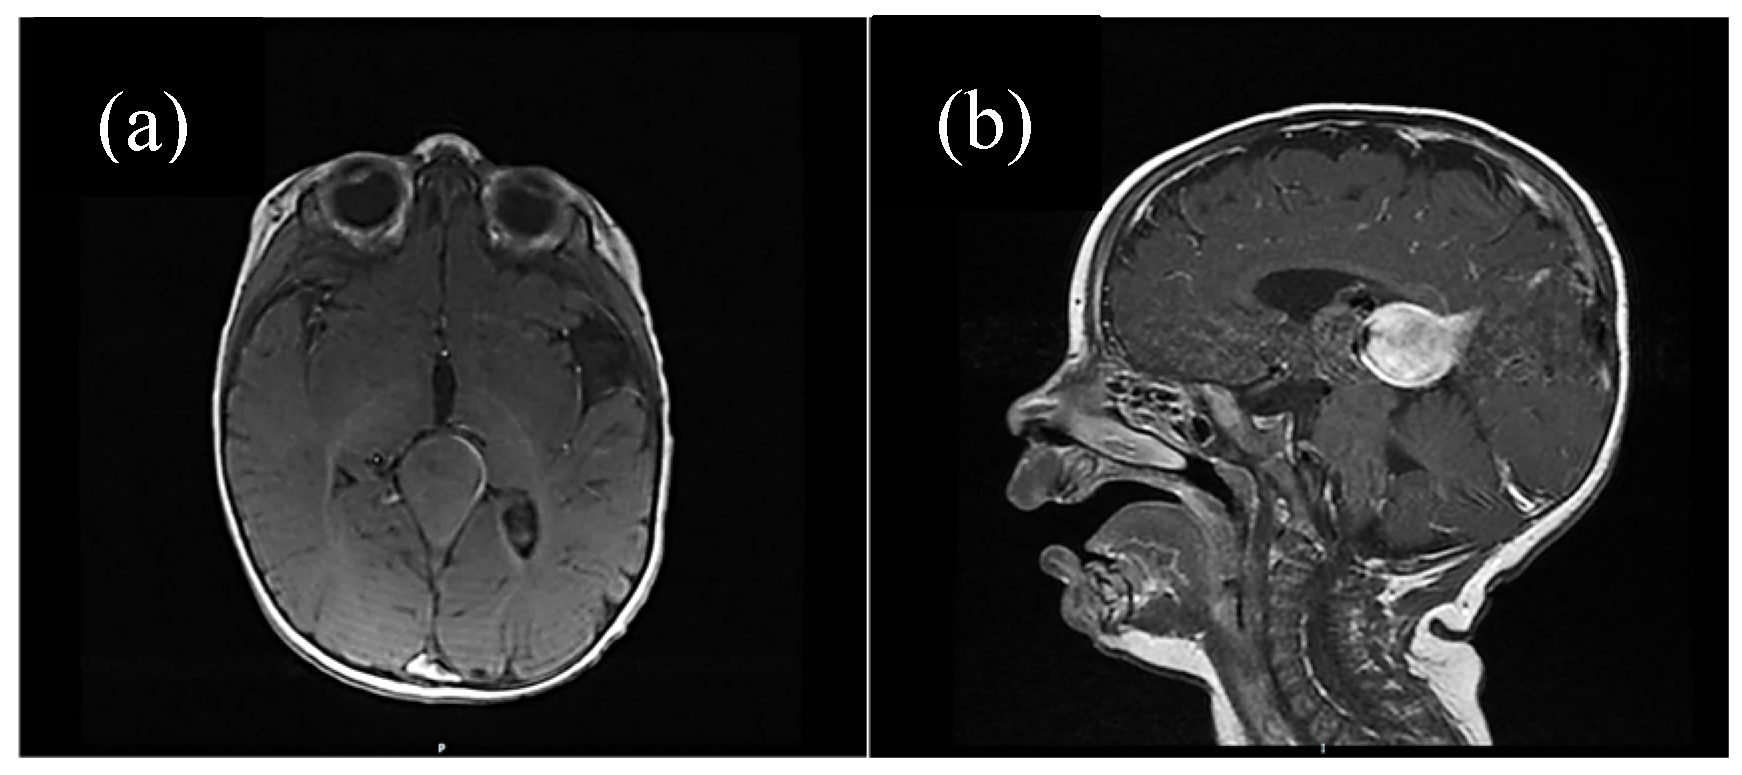

Half of the patients were diagnosed antenatally (by ultrasound or fetal MRI) and half of them postnatally, most frequently by cerebral ultrasound or after auscultation of a cardiac murmur followed by heart ultrasound displaying diastolic steal from the thoracic or descending aorta into the carotid territory towards cerebral circulation. The general aspect described was that of a saccular structure located at the level of the quadrigeminal tank with both arterial and venous Doppler signals, communicating with the large cerebral sinuses and having numerous arterial and venous collaterals (see Figure 1 and Figure 2).

Figure 3. (a) Native cerebral MRI (transverse section), (b) contrast cerebral IRM (sagittal section). Vascular aneurysmal dilation at the level of the quadrigeminal tank, with no significant compressive effect, no thrombosis, no infra/supratentorial lesions. Asymmetrical ventricular system but normally positioned midline structures. Ependymal cyst located in the atrium of the LV. Asymmetry of the temporal lobes due to incomplete gyration.